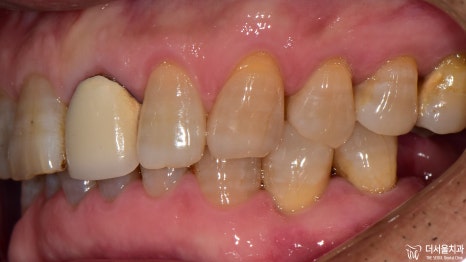

자, 이제는 썩은 치아 곳을 진료해 드릴 차례입니다.

감염된 곳에 작은 홀을 뚫어

치수로 접근할 수 있는 통로를 만들어 주었습니다.

이제 결과를 보여드릴 차례네요.

모든 보철을 지르코니아를 사용하여

심미성을 한껏 더해주었습니다.

이렇게 몇 곳만 바뀌어도

가만히 있던 주변 치아들까지

좀 더 건강하고 활기차 보이지 않나요?

환자께서는 오랜만에

맛있는 음식을 먹을 수 있겠다며

멋있는 미소를 지어주셨습니다^^